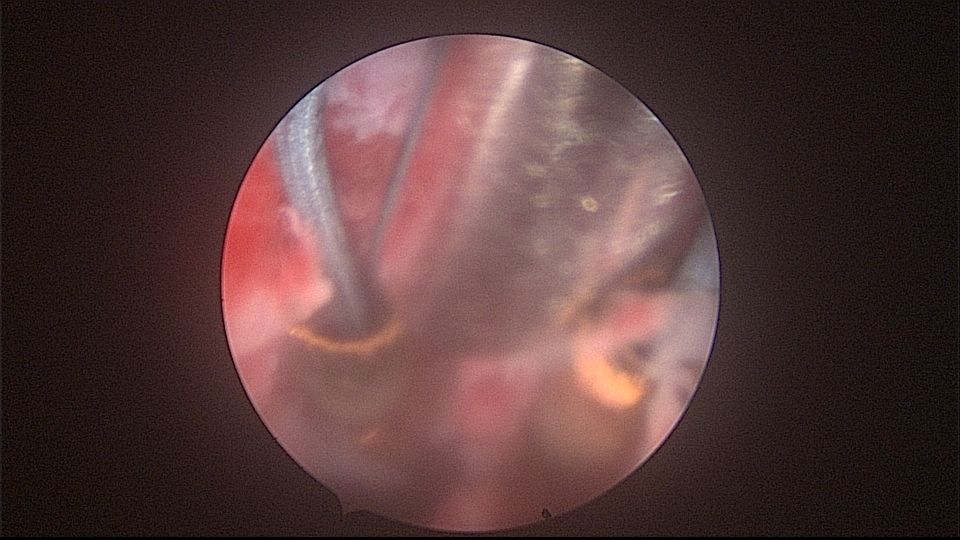

患者52岁,G2P1,顺产1次。安环27年,外院取环失败。病人肥胖,B超提示子宫前位,节育环距宫底0.9cm。子宫极度前倾前屈位,宫腔镜见宫颈管组织杂乱,宫颈管上段右前壁见假道,膨宫不良,视野模糊,寻找宫腔方向困难,准备B超监护过程中,拆走扩阴器,腹部下压子宫,终于寻找到了宫颈内口,看到了爱母环下端,异物钳牵拉出节育环,再次探查宫腔,无其他异常。